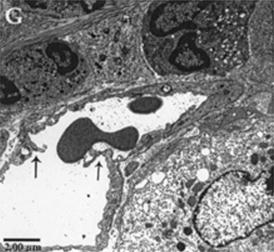

Electron Microscopic Evidence

Electron microscopy (EM) studies on the skin of the Tg mice revealed important ultrastructural changes in the microvascular beds [39]. Under transitional electron microscopy (TEM), the perivascular dermal matrix of NT mice consists of fibroblasts, collage and mast cells. NT mice have dermal blood capillaries that are continuous and formed by 1-2 endothelial cells (EC) with regular and smooth surfaces (Fig. 6.5a). In contrast, Tg mice dermal EC exhibit progressive nucleoli hypertrophy, cytoplasmic vacuolation, organelle hyperplasia, and increase in cell surface irregularity, thus demonstrating an endothelial cell activation process (Fig. 6.5b–d). The extracellular matrix is also more edematous with increased erythrocyte extravasation. These ultrastructural alterations documented in the Tg mice are hallmarks of angiogenesis.

Fig. 6.5

TEM micrographs of dermal capillaries. Capillaries of the NT mouse has thin continuous endothelium with regular and smooth surfaces (a). The capillaries of the IL-4 Tg mouse at BO stage still has continuous endothelium, but are thicker, more irregular and vacuolated. The endothelial cell (EC) nucleus is enlarged with prominent nucleoli, a sign of EC activation in preparation for angiogenesis (b). As disease progresses from EL (c) to LL (d) the capillary endothelium becomes increasingly irregular and vacuolated; ECs become increasingly hypertrophic with large nuclei and nucleoli and enlarged cytoplasm (Reproduced with permission, Agha-Majzoub et al. [39])

Endothelial remodeling is the fundamental process responsible to angiogenesis and we also examined this process by EM in AD. Angiogenic capillaries are distinguished from nonangiogenic capillaries by the presence of hypertrophied endothelial cells that appears activated with organelle rich cytoplasm and a minuscule lumen. In lesional skin of Tg mice, newly formed blood vessels form by intussusception, where interposition of transcapillary pillars allows division of one capillary into two separate capillaries (Fig. 6.6), whereas such observation is absent in NT mice. In Tg-EL and Tg-LL mice, both angiogenic and non-angiogenic capillaries were present.